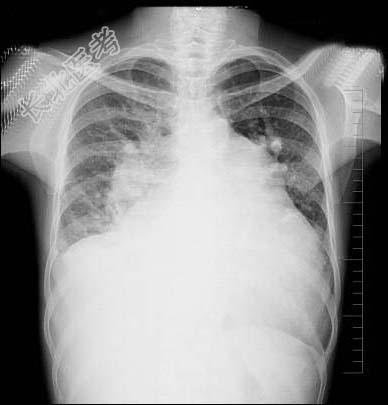

- 多项选择题47岁女性患者,诊断风湿性二尖瓣狭窄3年余, 近来呼吸困难,咳泡沫痰, 拍胸部正位片如图所示,下列关于肺部描述和结论正确的是 ( )

A、双侧肺纹理增强

B、双侧上下肺静脉比例倒置

C、肺门影模糊

D、肺野透亮度减低

E、考虑肺淤血